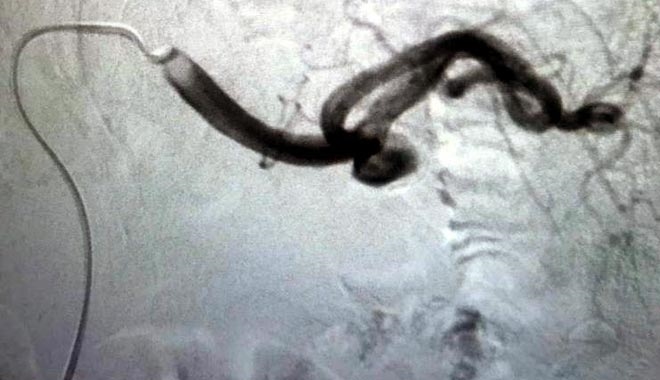

Kayseri Şehir Hastanesi´nde uygulanan periferik arterlerde anevriz tedavisi ile açık ameliyata gerek kalmadan hastalar şifaya ulaşıyor.

Kayseri Şehir Hastanesi´nde uygulanan periferik arterlerde anevriz tedavisi, hastaların iyileşmesinde etki gösteriyor. Karın ağrısı nedeniyle Kayseri Şehir Hastanesine başvuran hasta, yapılan tetkikler sonrası splenik arterinde halk arasında baloncuk olarak bilinen anevrizmatik genişleme olduğu saptandı. İleri tetkik ve tedavi için girişimsel radyoloji ünitesine yönlendirilen hastaya, periferik arterlerde anevriz tedavisi uygulandı.

Kayseri Şehir Hastanesi Girişimsel Radyoloji Uzmanı Doktor Mustafa Özdemir´in yaptığı tedavide, hastanın kasığından girilerek genişlemiş damar bölgesi içine ulaşıldı ve anevrizma kapatıldıç 1.5 saat süren işlem sonrasında hasta, 1 gün gözlem altında tutulduktan sonra taburcu edildi ve normal hayatına döndü.

Yapılan açıklamada, bu hastanın açık ameliyat ile tedavi olması durumunda ameliyat süresi ve sonrası hastanede yatış süresi daha uzun olacağı ve normal hayatına dönme süresinin 15-25 gün sürebileceği bildirildi.